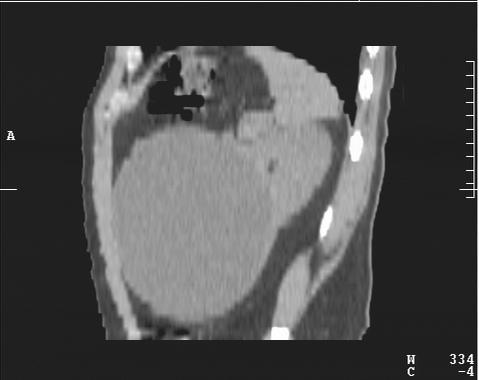

М. 37 лет, жалоб нет, амб. приём, причина назначения УЗИ ОБП: СОЭ 42мм

б\б и м\э консист., как говорится.   Исходит из н\ полюса левой почки

Вложения

2.JPG

3.JPG

4.JPG

КТ сделали без контрастирования, смысл такого КТ??? Диагностической ценности-ноль.